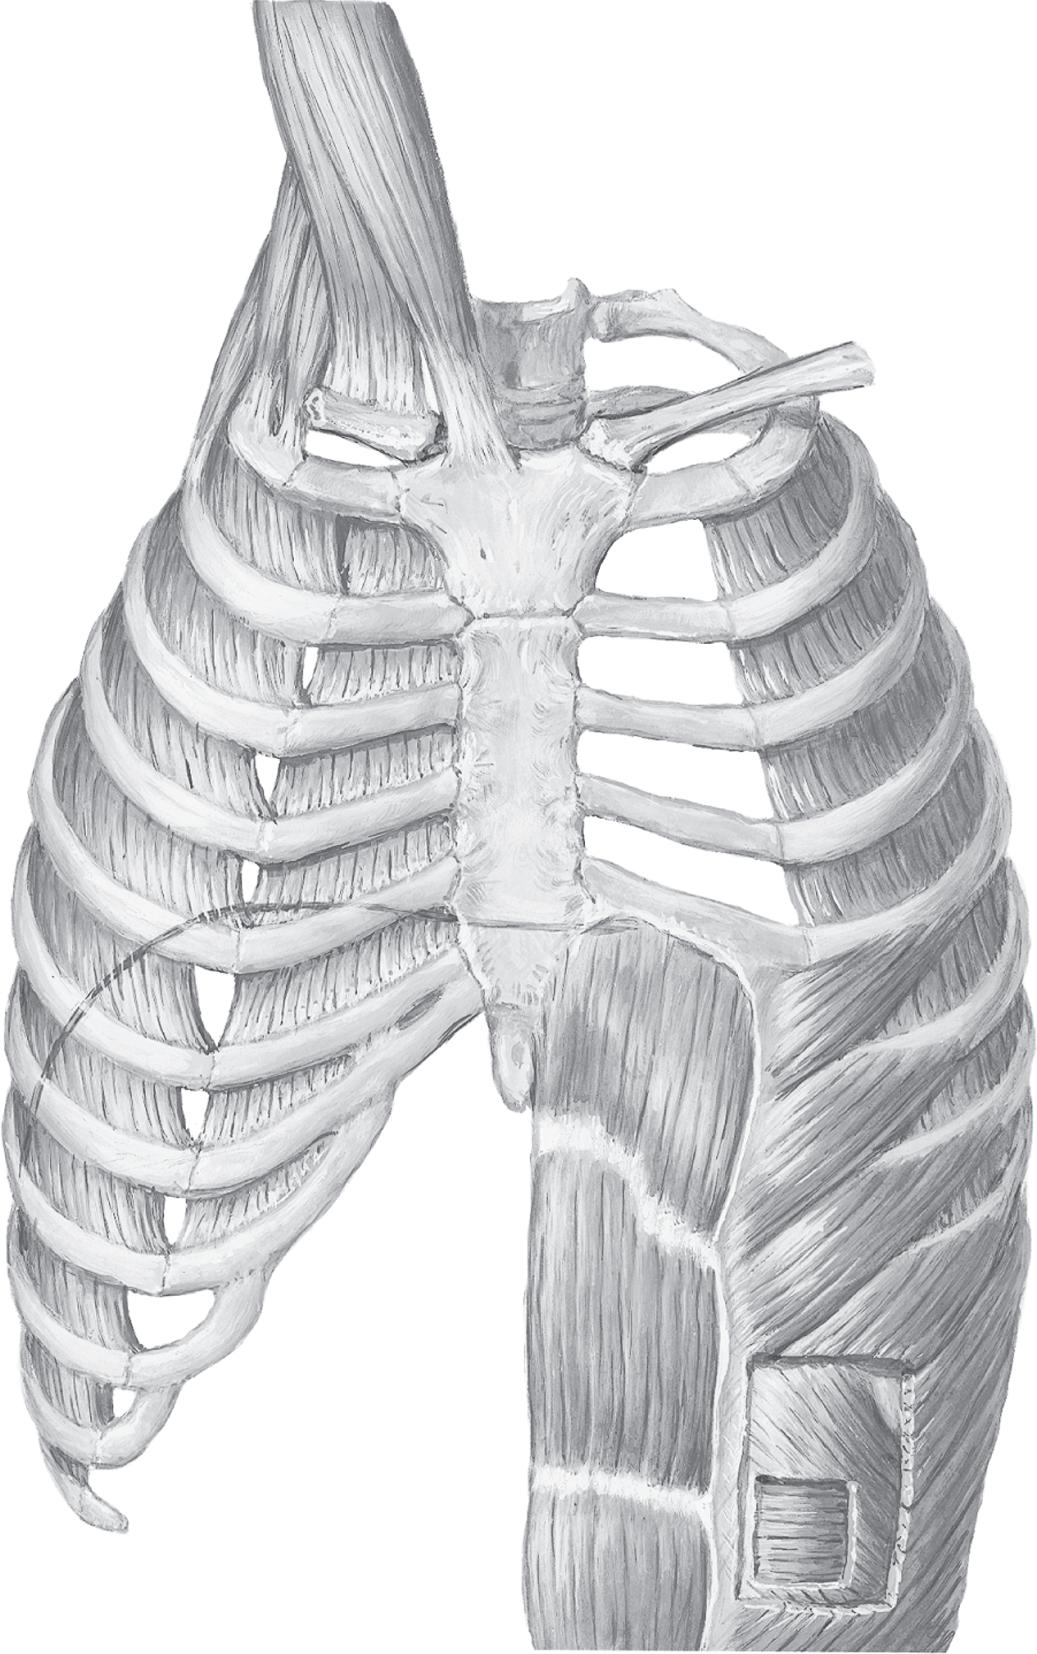

Therespiratorysystemiscomposedofthlungs·the upperandlowerairways,includingthenose;hechestwall, includingthemusclesofrespiration(diar,hrag,intecostalmuscles,andabdominalmuscles)andthvribcage;the pulmonarycirculation;andthosepartsofthecentralnervoussystemthatregulaterespiration(ig.1.1).

Dividing the thoracic cavity from the abdominal cavity is the diaphragm, the major muscle of respiration (Fig. 1.11). The diaphragm is a thin, musculotendinous, domeshaped sheet of muscle that is inserted into the lower ribs and separates the thoracic from the abdominal cavity. It is supplied by the phrenic nerve that arises from the second cervical vertebra. When it contracts, the abdominal contents are forced downward and forward and the vertical dimension of the chest cavity is increased. In addition, the rib margins are lifted and moved out, causing an increase in the transverse diameter of the thorax. In adults, the diaphragm is capable of generating airway pressures of 150 to 200 cm H2O during a maximal inspiratory effort. During quiet breathing (known as tidal volume breathing), the diaphragm moves approximately 1 cm, but during large-volume breathing, the diaphragm can move as much as 10 cm. If the diaphragm is paralyzed, it moves higher up in the thoracic cavity during inspiration because of the fall in intrathoracic pressure. This paradoxical movement of the diaphragm can be demonstrated using the radiographic technique called fluoroscopy.

The other significant muscles of inspiration are the external intercostal muscles that pull the ribs upward and forward during inspiration, causing an increase in both the side-toside and front-to-back diameters of the thorax (Fig. 1.12). Innervation of these muscles originates from intercostal nerves that originate from the spinal cord at the same level. Paralysis of these muscles has no significant effect on respiration because of the dominance of the diaphragm as the major muscle of respiration. Accessory muscles of inspiration (scalene muscles, which elevate the sternocleidomastoid; the alae nasi, which cause nasal flaring; and small muscles in the neck and head) are quiet during quiet breathing but contract vigorously during exercise and with significant airway obstruction.

Exhalation during quiet breathing is passive but becomes active during exercise and hyperventilation. The most important muscles of exhalation are those of the abdominal wall (rectus abdominis, internal and external oblique, and transversus abdominis) and the internal intercostal muscles that oppose the activity of the external intercostal muscles (i.e., pull the ribs downward and inward).

Muscles of inspiration

Accessory

Sternocleidomastoid (elevates sternum)

Scalenes

Anterior Middle Posterior (elevate and fix upper ribs)

Principal

External intercostals (elevate ribs, thus increasing width of thoracic cavity)

Interchondral part of internal intercostals (also elevates ribs)

Diaphragm (domes descend, thus increasing vertical dimension of thoracic cavity; also elevates lower ribs)

MUSCLES OF RESPIRATION

Muscles of expiration

Quiet breathing

Expiration results from passive recoil of lungs and rib cage

Active breathing

Internal intercostals, except interchondral part

Abdominals (depress lower ribs, compress abdominal contents, thus pushing up diaphragm)

Rectus abdominis

External oblique

Internal oblique

Transversus abdominis

Fig. 1.12 Muscles of respiration. Diagram of the anatomy of the major respiratory muscles. Left side, inspiratory muscles; right side, expiratory muscles. (Kaminsky D. The Netter Collection of Medical Illustrations: Respiratory System, vol. 3, 2nd ed. Philadelphia: Elsevier; 2011.)